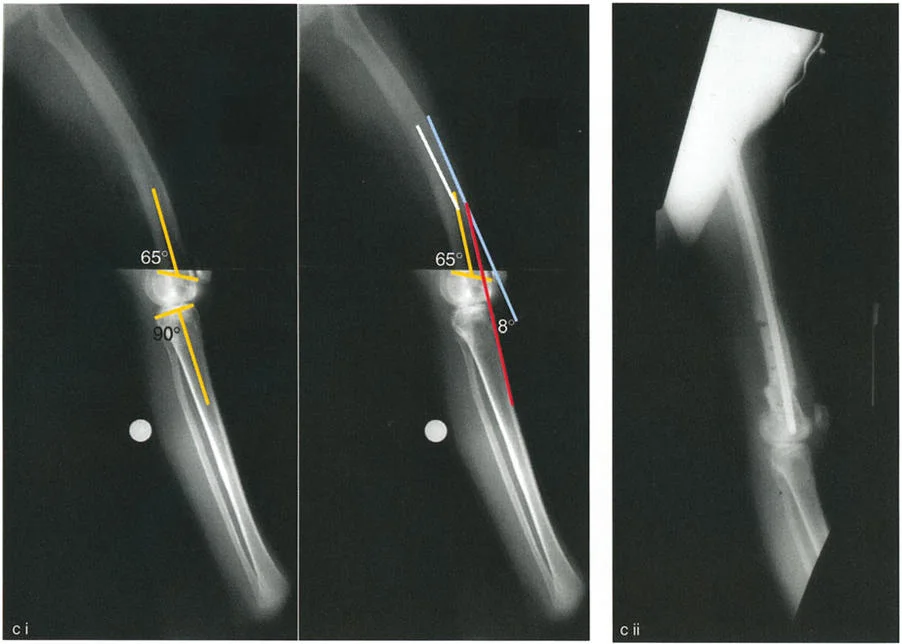

- الأشعة السينية الطويلة للطرف السفلي بالكامل أثناء الوقوف (Standing Long-Leg AP View): تُعد هذه الأشعة حاسمة لتقييم المحاذاة الميكانيكية للطرف السفلي بأكمله. تُظهر بدقة درجة الانحراف الأفحج (Varus) أو الأروح (Valgus) وتساعد في تحديد مركز دوران التشوه (CORA).

- الأشعة الجانبية الطويلة للطرف السفلي بالكامل أثناء الوقوف في أقصى بسط (Standing Long-Leg Lateral View in Maximum Extension): تُستخدم لتقييم تحدد حركة الركبة (FFD) والركبة الارتدادية (Recurvatum)، وتحديد ما إذا كان التشوه عظميًا أو ناتجًا عن تقلص في الأنسجة الرخوة.

تصحيح تحدد حركة الركبة (Flexion Deformity - FFD)

تحدُّد حركة الركبة هو عدم القدرة على مد الركبة بالكامل. يمكن أن يكون سببه عظميًا أو ناتجًا عن تقلص في الأنسجة الرخوة.

- التشخيص الدقيق: يجب تحديد ما إذا كان تحدد الحركة ناتجًا عن تشوه عظمي (تقوس أمامي في الفخذ أو الساق) أو تقلص في الأنسجة الرخوة (الأوتار الخلفية، محفظة المفصل).

- قطع العظم التمديدي (Extension Osteotomy):

- إذا كان التشوه عظميًا، يتم إجراء قطع عظم تمديدي في عظم الفخذ أو الساق لتصحيح التقوس.

تصحيح الركبة الارتدادية (Recurvatum Deformity - Hyperextension)

الركبة الارتدادية هي فرط البسط في الركبة. غالبًا ما تكون غير مصحوبة بأعراض في الأشخاص ذوي العضلات السليمة، ولكنها قد تسبب مشاكل في حالات ضعف العضلات أو التشوهات العظمية.

- التشخيص: يجب تحديد ما إذا كانت الارتدادية عظمية (تقوس خلفي في الفخذ أو الساق) أو ناتجة عن رخاوة في الأنسجة الرخوة أو ضعف عضلي.

- قطع العظم الانثنائي (Flexion Osteotomy):

- إذا كان التشوه عظميًا (تقوس خلفي)، يتم إجراء قطع عظم انثنائي في عظم الفخذ أو الساق لتصحيح الارتدادية.